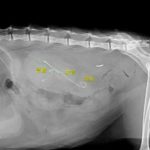

急性腎機能障害の猫ちゃんが(BUN>130mg/dl、Cre>14mg/dl、高カリウム血症)治療のため救急で対応しました。無麻酔CTでは両側に尿管結石が確認されました。著しく拡張している左腎の腎盂に一時的な腎瘻カテーテルを設置し、尿の排泄路の確保を行います。しかし、腎数値に改善は見られませんでした。腎盂造影を行うと拡張している腎臓において尿の産生と排泄は行われている様です。一方、腎盂拡張のほとんどない右腎の腎盂造影では尿の排泄が確認されません。今回の急性腎機能障害の原因は機能の残っていた右腎の急性尿管閉塞による急性腎障害と診断しました。左腎に関しては尿の産生はあるものの慢性腎機能障害であり、すでに尿濃縮能は失われていると判断しました。右腎の問題に対して尿管膀新吻合短尺型ステント設置術を行いました。術後は徐々に腎数値は低下し、腎機能の回復が得られました。一見すると腎盂拡張の顕著な側が急性腎障害の責任病変と判断しがちですが、片腎が十分に機能していれば腎数値に影響はほとんどなく、どちらの腎臓を治療対象とするか?エコー、CTなどの画像診断、血液検査、一時的な腎瘻カテーテルの設置、腎盂造影など総合的な判断が必要です。また判断がつかず、左右同時に治療が必要な場合もあります。